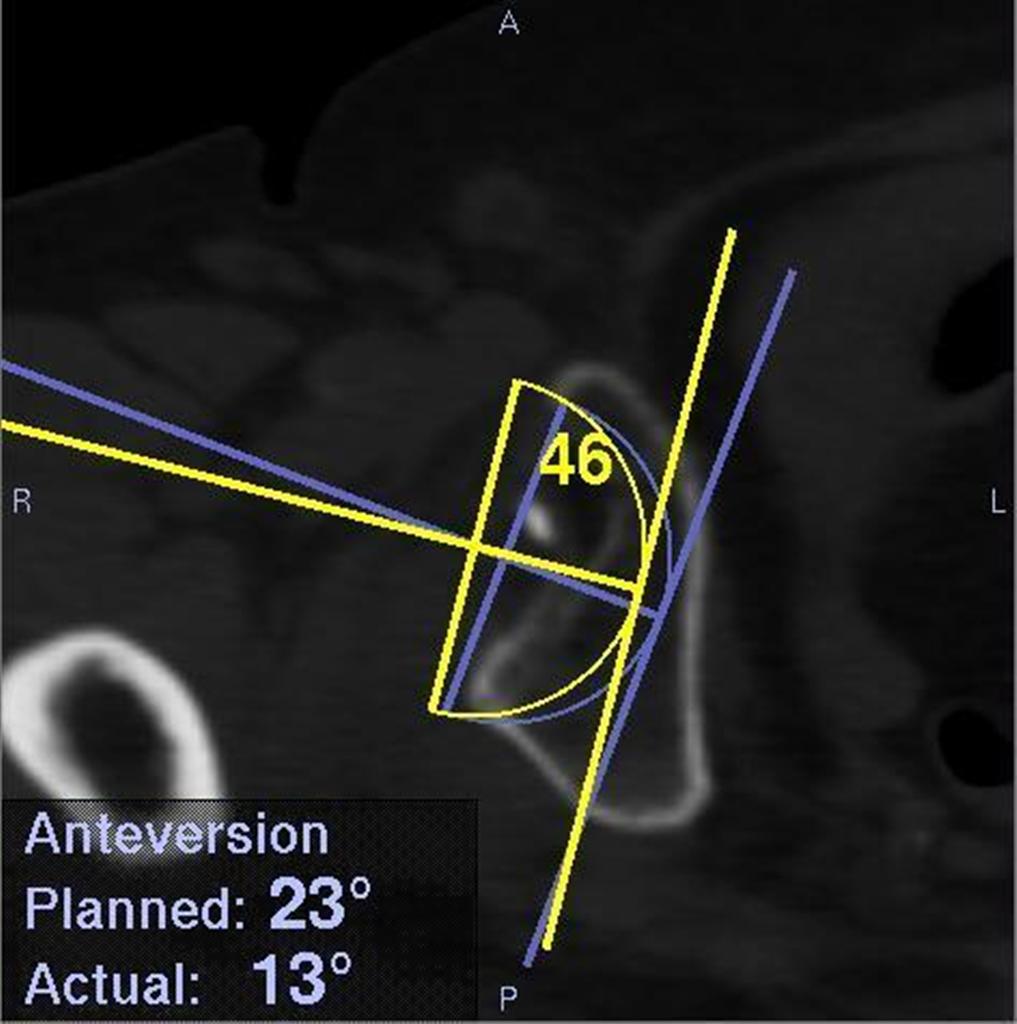

ナビゲーションシステムのモニター画面の一部。実際に人工関節を挿入した角度と位置、当初の計画値も表示されるため、ずれの程度が分かる